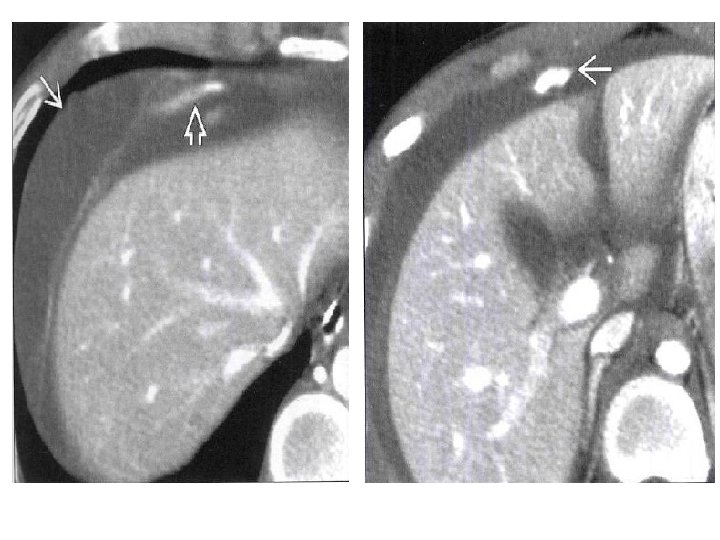

Trauma hepático – outros achados

Trauma hepático – achados na TC • Lacerações: – Simples: lesão hipodensa linear solitária; – “Estrelada”: lesões hipodensas lineares ramificadas (paralela aos ramos da veia porta ou hepática) – Superficial: < 3 cm; profunda: > 3 cm • Hematoma: parenquimatoso x sucapsular (formato lenticular) – Não coagulado (menos tempo): hiperdenso em relação ao parênquima hepático não contrastado e hipodenso em relação ao contrastado – Coagulado: mais denso que o não coagulado

Hemorragia ativa: área focal de atenuação de contraste em fase arterial. Se persistir: falha no tratamento conservador